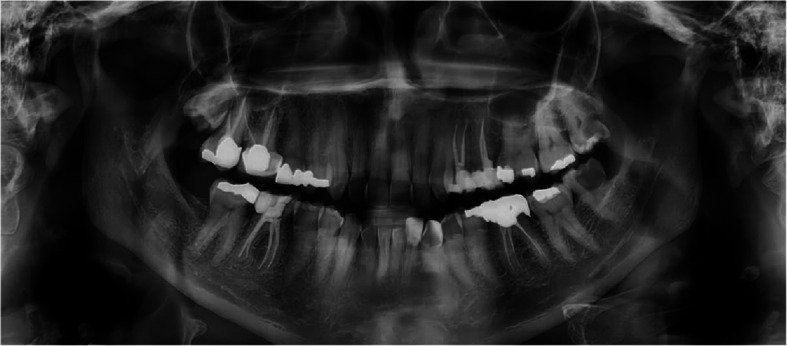

Background: Carotid artery calcifications and pulpal stones are radiopaque findings that may be found accidentally in panoramic views. The risk of affliction with atherosclerotic events in diabetic patients with dystrophic calcification is questionable. This study aimed to investigate the relative frequency of carotid calcifications and pulp stones in panoramic radiographs of diabetic patients.

Results: In this study, panoramic radiographs of 107 diabetic patients (67 women and 40 men) and 300 healthy individuals (196 women and 104 men) were evaluated. The age range was 25 to 64 years, with a mean age of 49.7. The frequency of carotid artery calcification was 42 (14%) in healthy individuals and 44 (41.1%) in diabetic patients. Furthermore, the relative frequency of unilateral and bilateral carotid artery calcification in diabetic patients was significantly higher than in healthy subjects (P < 0.05). The Relative Risk (RR) of pulp stones in the diabetic patient group compared to healthy individuals was 1.8. With a 95% confidence interval, the relative risk ranged from 1.3 to 2.48, which was statistically significant (P < 0.05).

Conclusions: Based on the findings, the frequency of carotid artery calcification and pulp stones was higher in diabetic patients. Panoramic radiographic screening in diabetic patients is useful for early detection of carotid artery calcification and timely referral of patients to endocrinologists to prevent adverse sequelae.